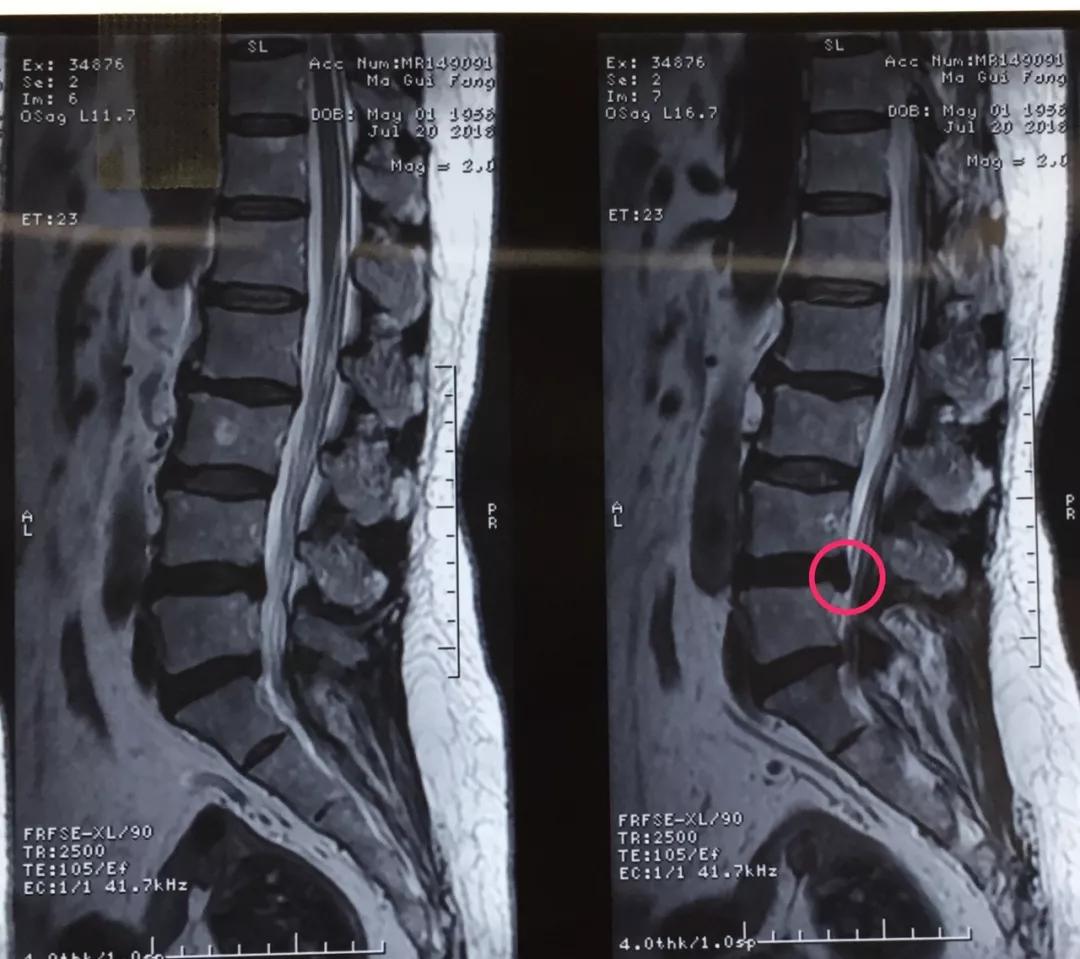

60岁的人生状态应该是退休在家,带着孙子孙女享受天伦之乐,而同样是60岁的马老太,被腰椎间盘突出症困扰了多年,稍微劳累就腰背酸痛,近几个月来又开始出现左下肢的过电样抽痛,抽的腿都抬不起来,家人带着马老太到医院做了检查说是腰椎间盘突出症,问了几家医院都说要来开刀手术,卧床两月,这下把马老太吓住了,一边是病痛折磨,一边是对手术的恐惧,正绝望之际,邻居建议马老太到六合彩生肖 郭华副院长的专家门诊看一下,马老太并没有抱太大希望,那么多医院都说要手术,估计治疗方案是一样的,手术是免不了了。到中心医院后,郭华副院长仔细地询问了马老太的病史,并进行了细致的查体,然后看了看片子,对马老太说:“你这个情况确实是腰椎间盘突出症,但是不需要全麻开大刀,局麻下1cm小口把椎间盘取出来就可以了,术后就可以直接下地走路了,而且你现在检查齐全了,当天住院、当天手术、当天出院,我们叫做——椎间孔镜日间手术”,马老太半信半疑的回家考虑了几天,最终马老太还是相信中心医院的实力,24日马老太入住骨一科后,郭华副院长、严少荣主任、姬钢主任医师中午共同为马老太局麻下实施了经皮椎间孔镜下髓核摘除术,手术共计一小时,手术完马老太抬腿就不痛了,郭华副院长告诉马老太,你这个情况完全可以出院走路回家了,可把马老太高兴坏了。

郭华副院长介绍:随着人口老龄化,腰椎间盘突出症的发病数量越来越多,而医学的进步也同样日新月异,传统的开大刀手术越来越少,六合彩生肖 开展的经皮椎间孔镜下髓核摘除术(PELD)是近几年来成熟起来地一种微创手术方式,局麻下不到一小时就可以取出压迫神经根的椎间盘,术后即刻解除疼痛下地走路,甚至可以做到日间手术(当日住院、当日手术、当日出院),医保报销后花费少,效果立竿见影,得到了广大患者的认可和好评。希望医学德进步给广大病患带来福音,希望六合彩生肖 的新技术能为更多的病人解除病痛。